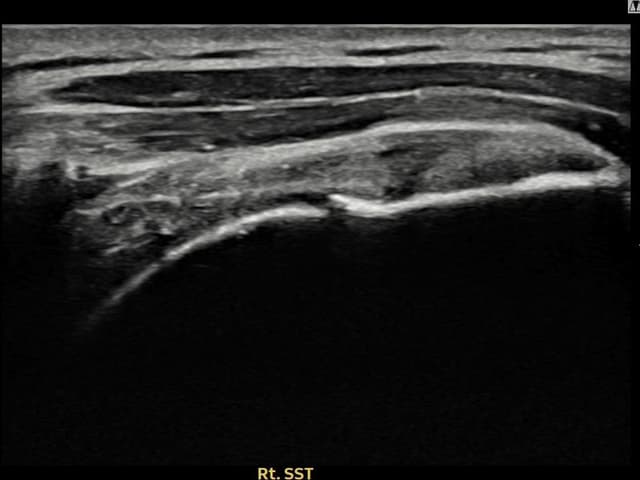

右侧 冈上肌腱 石灰化肌腱炎

13mm × 9mm